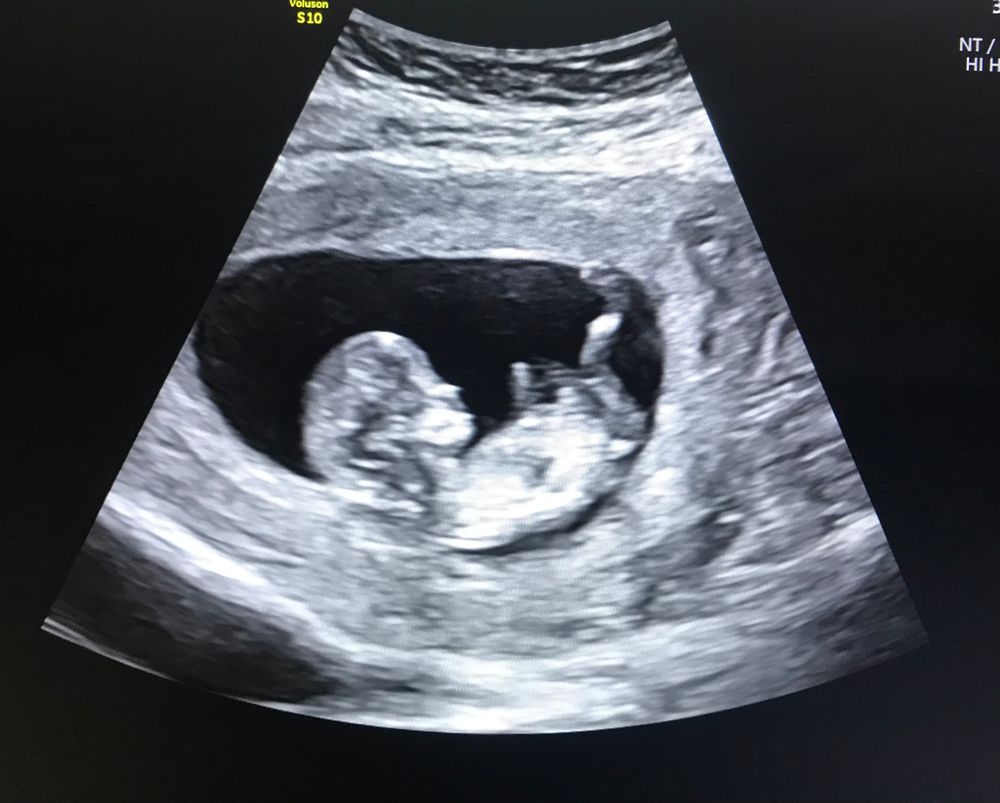

17 неделя.

•Уже был первый скрининг. Малыш соответствует всем нормам развития. Правда, как и в первую беременность поставили риск Прекламсии. Пью кардиомагнил.

P.S. По фото узи, кажется что нос в этот раз от мужа, а ножки коротенькие -мои😅. С Василисой было наоборот. Всю беременность мне твердили, что у неё просто модельные длинные ноги. Так и вышло. Ножки просто шикарные 😍